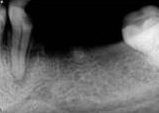

antes depois